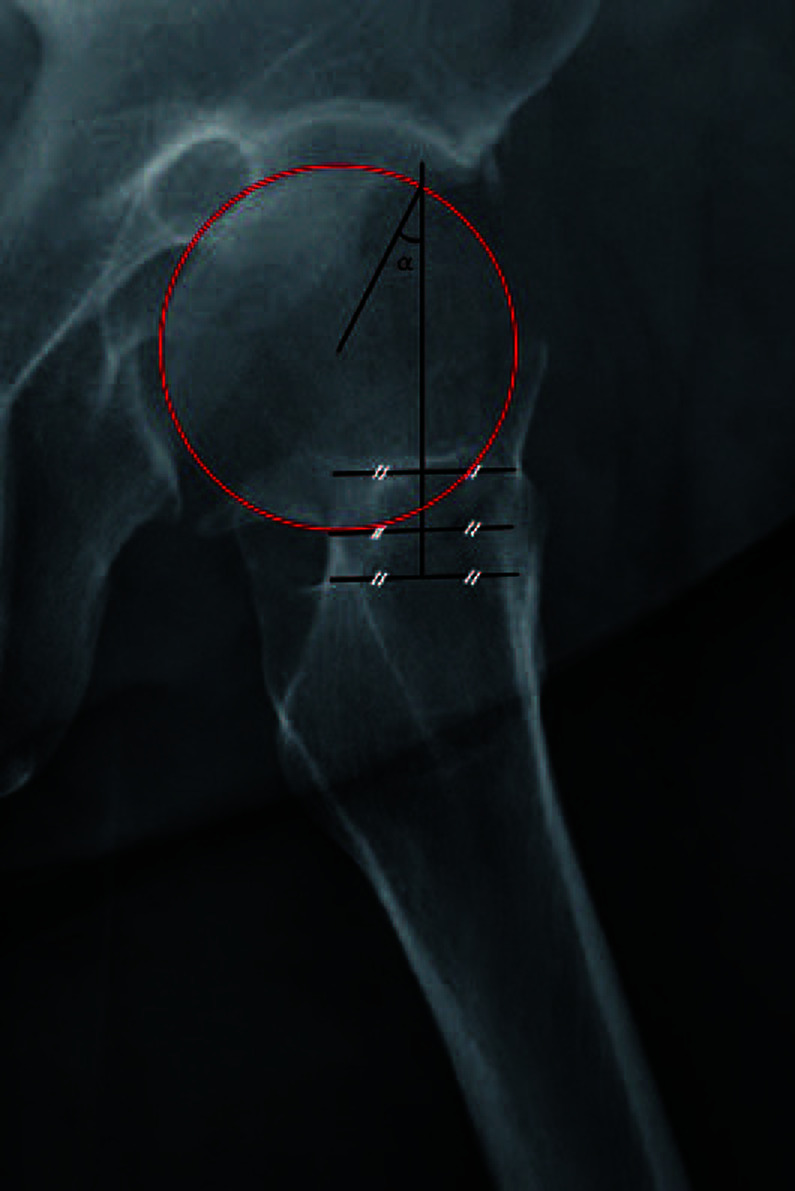

Purpose: Nondisplaced femoral neck fractures have traditionally been treated with in situ fixation. However, poor surgical and clinical outcomes have been reported for fractures with valgus deformity >15°, and the reduction of valgus impaction has recently been emphasized. In addition, early degenerative osteoarthritis can be caused by cam-type femoroacetabular impingement after healing of femoral neck fractures. This study was designed with the objective of confirming the difference in progression of radiographic osteoarthritis according to the severity of the valgus deformity.

Materials and methods: Patients who underwent internal fixation using multiple cannulateld screws for management of nondisplaced femoral neck fractures were divided into two groups: high valgus group (postoperative valgus angle ≥15°) and low valgus group (postoperative valgus angle <15°). Evaluation of demographic data and changes in the joint space width from the immediate postoperative period to the latest follow-up was performed.

Results: A significant decrease in joint space width in both hip joints was observed in the high valgus group when compared with the low valgus group, including cases with an initial valgus angle less than 15° and those corrected to less than 15° of valgus by reduction. No complications requiring surgical treatment were observed in either group; however, two cases of avascular necrosis, one in each group, which developed in the low valgus group after reduction of the fracture, were followed for observation.

Conclusion: Performing in situ fixation in cases involving a valgus deformity ≥15° in non-displaced femoral neck fractures may cause accelerated narrowing of the hip joint space.